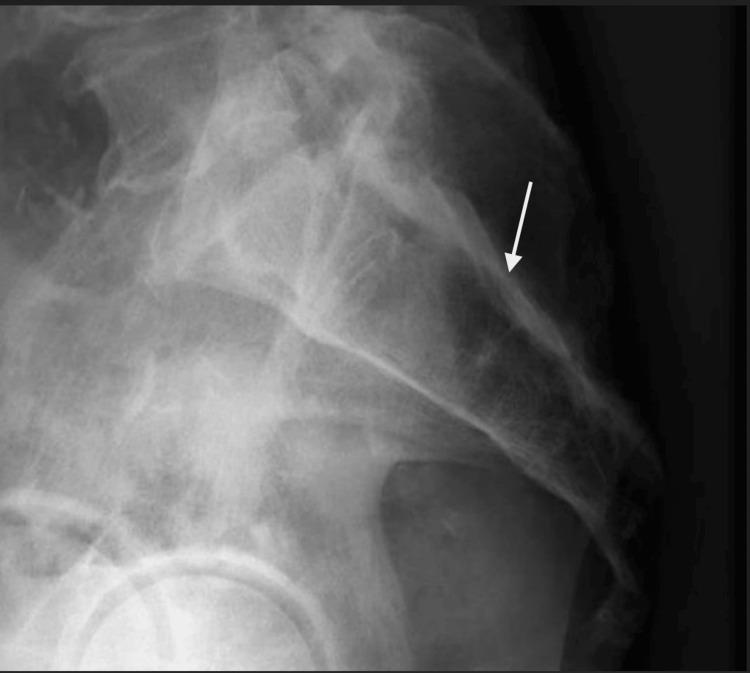

Sacral osteomyelitis is an infection of the bone that extends posterior to the pelvis at the base of the spine. This condition typically occurs in elderly or bedbound/immobile patients and is treated with wound debridement, wound care, surgery, and antibiotic therapy. In this report, a case is presented of a rare complication of sacral osteomyelitis where the infection extended through the bone into the spinal canal causing an ascending spinal canal infection. This report is meant to provide an individual example of this rare complication which can hopefully be used to improve surveillance, treatment, and outcomes of this rare condition.